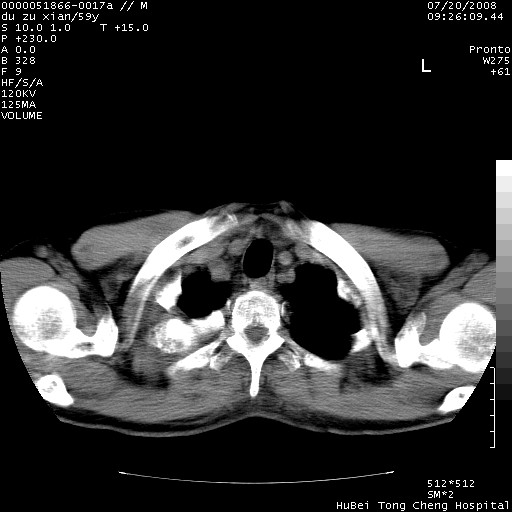

以下是引用宇宙ct在2008-8-25 23:21:00的发言:[br]右肺周围性肺癌并肋骨转移,纵隔淋巴结转移。

以下是引用zsl6918在2008-8-25 22:40:00的发言:[br]右肺周围性肺癌并肋骨转移,纵隔淋巴结转移。

以下是引用zy_zj在2008-8-26 15:24:00的发言:[br]单从病变本身,我倾向良性炎性病变,但肋骨转移了,所以说是考虑右肺周围性肺癌并肋骨、纵隔淋巴结转移可能性大。